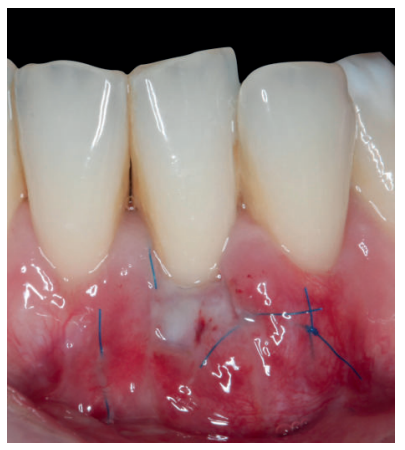

Previamente a la intervención, la paciente se enjuagó durante un minuto con un colutorio de clorhexidina. La técnica quirúrgica comenzó con la preparación del lecho receptor, se realizaron incisiones intrasulculares a nivel cervical hasta la línea ángulo de todos los dientes del frente antero-inferior (33-43), desinsertando la base de la papila sin seccionarla con la ayuda de instrumentos de tunelización. Posteriormente se realizó una incisión en el fondo de vestíbulo (Figura 11). A continuación, se obtuvo un injerto de tejido conectivo del paladar introduciéndolo en el lecho receptor, siendo todas las suturas realizadas de la misma manera que en el caso clínico 1, usando tanto material reabsorbible como no reabsorbible de 5/0 y 6/0 ceros (Figura 12).

El control a la semana (Figura 13) presentaba inflamación moderada y a las 2 semanas (Figura 14) se retiraron los puntos de sutura. La paciente acudió a los 4 meses (Figura 15) y al año (Figura 16) a visitas de revisión, donde se apreció una buena banda de tejido queratinizado y una pequeña cicatriz.